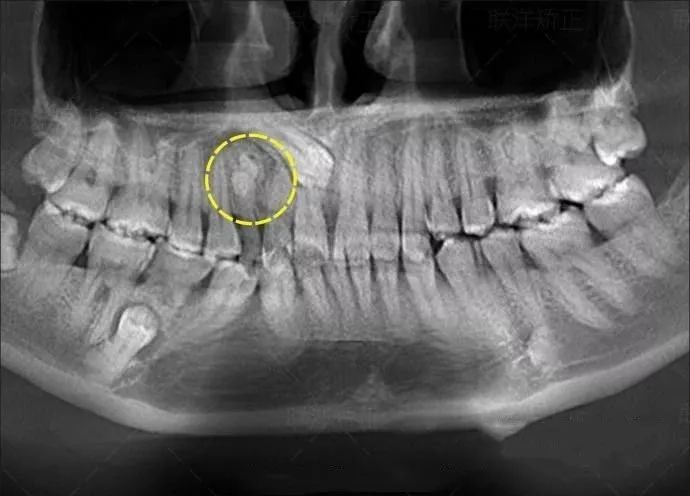

牙齿的牙根是埋在牙槽骨中的,医生没有透视眼,为了解患牙的牙根的形态、走向、长度及根尖周有无病变及病变大小,或者怀疑有肉眼无法确认的其它牙科问题,都会建议患者去牙科的X光,甚至,口腔CT来全面性地确认问题,以订定合适的治疗计划。

拍一次全口曲面断层

=22微西弗

=22张小牙片

=220根香蕉

等于坐飞机5.4小时

拍一次全口曲面断层=吃220根香蕉